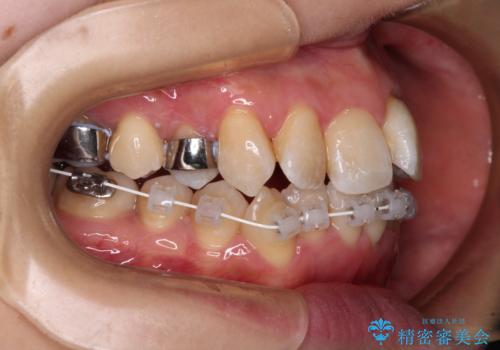

2. 治療途中

2. 【モニター】急速拡大装置 狭い歯列を拡大してワイヤー装置で短期間治療の治療中